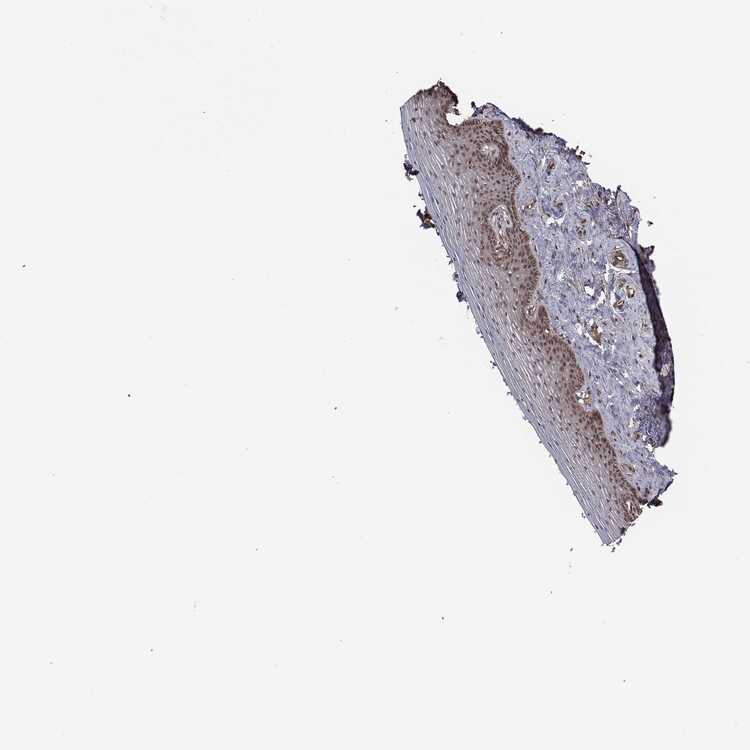

VAGINA - Antibody stainingi

Antibody staining in the annotated cell types in the current human tissue is reported as not detected, low, medium, or high, based on conventional immunohistochemistry profiling in selected tissues. This score is based on the combination of the staining intensity and fraction of stained cells.

Each image is clickable and will lead to virtual microscopy that enables deeper exploration of all samples and also displays staining intensity scores, fraction scores and subcellular localization as well as patient and tissue information for each sample.

Antibody HPA048606Antibody HPA059863

Squamous epithelial cells Not detectedLow